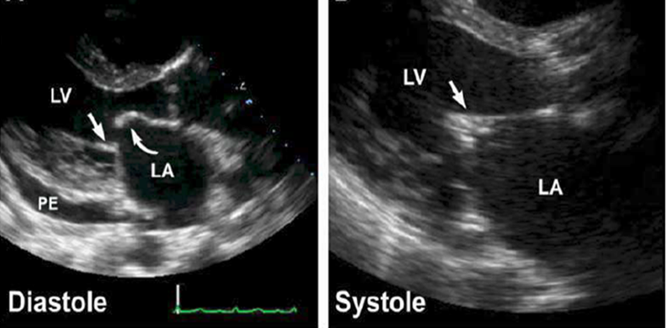

what is this?

mitral stenosis (hockey stick)